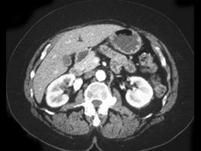

问题 男,68岁,偶然发现高血压,请根据所示图像,选择最可能诊断 ( )

选项 A、右肾血管瘤 B、右侧肾上腺嗜铬细胞瘤 C、右肾囊肿合并出血 D、右肾动脉瘤 E、右肾出血

答案 D